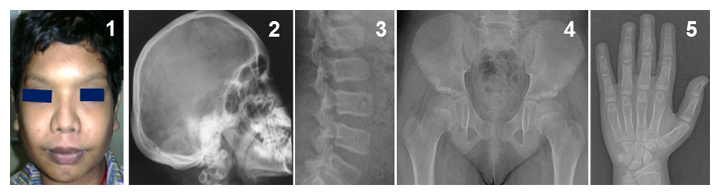

新たなタイプの骨の難病、Ikegawa型頭蓋管状骨異形成症のレントゲン像

また、運動器の遺伝性難病の医療と研究のために「骨系統疾患コンソーシウム」を設立し注2)、骨格、運動器の遺伝性難病の臨床データを世界中から収集してきました。その中に、共通の骨格異常を持つ4家系5人の患者を発見しました。これらの患者には、頭蓋骨の骨濃度の上昇、脊椎の形成異常、長管骨と短管骨の骨幹部の拡大などの特徴的な異常が認められました(図1)。このような骨格異常の組み合わせは過去に報告がなく、新たな疾患として「Ikegawa型頭蓋管状骨異形成症(Craniotubular dysplasia, Ikegawa type)」と名付けました。

図1 Ikegawa型頭蓋管状異形成症の表現型

頭蓋骨と管状骨(長管骨、短管骨)の肥厚、骨濃度の上昇などの特徴が見られる。

- 1前額部突出、眼間距離の拡大など特徴的な顔貌。

- 2-5特徴的なX線像。2肥厚した頭蓋骨、3脊椎椎体の扁平化、4大腿骨骨幹端部の短縮、5手の短管骨の骨幹部の拡大。